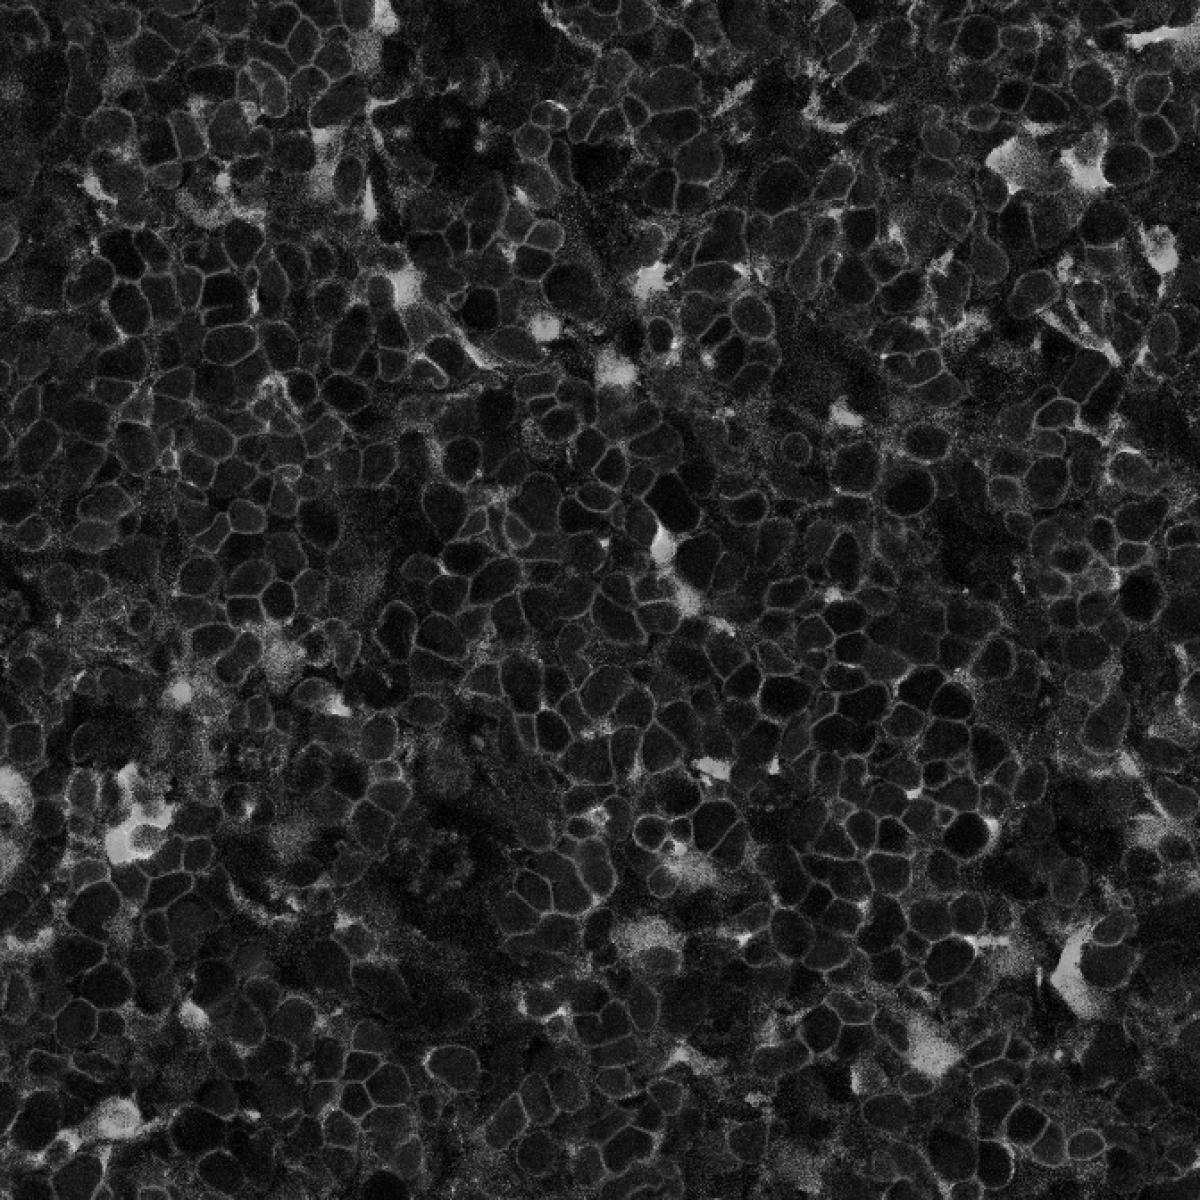

Hayes focuses on the basic and preclinical mechanisms of oncogene dependency and signal transduction, as well as the development of novel therapeutic approaches based on these insights. She develops innovative cell lines and organoid models to explore the role of signal transduction proteins in cancer. Her long-term research goal is to provide insights into MAPK signal transduction, revealing how normal cell signaling converts to aberrant states and how these disruptions are maintained in cancer.